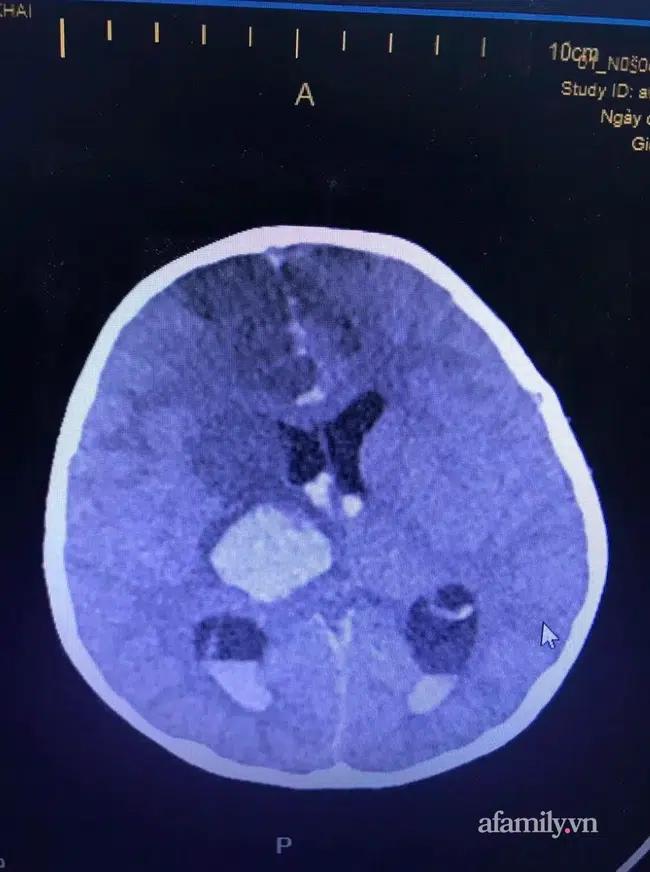

Trước đó như đã thông tin, ngày 22/12 bé K. được người nhà đưa đến BV trong tình trạng chảy nhiều máu, xuất huyết não, hôn mê... Kết quả chụp phim ghi nhận bé bị một vết thương dài từ hố mắt trái xuyên bán cầu não phải, chảy máu não.

Ảnh chụp phim vùng não bệnh nhi.